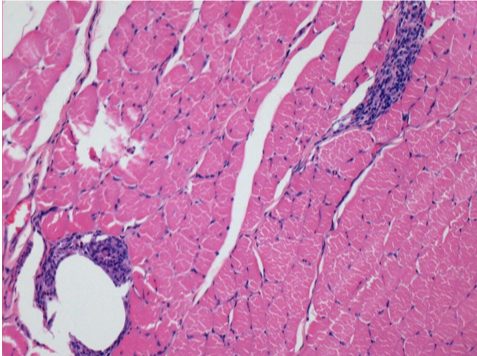

بعد شهر من حقن إندوبيل

بعد شهر واحد من حقن Endopeel 0.1 مل في العضلة أمام الظنبوب اليمنى.

ما يظهر باللون الأسود في الصور ليس نخرًا كما يتصور بعض العلماء!

في الواقع ، يجب أخذ 4 استنتاجات في الاعتبار :

- قطعة أثرية من التلوين

- عدم وجود نخر

- عملية بيولوجية

- موت الخلايا المبرمج

L : Control-100xD30

R:100xD30

R :400xD30